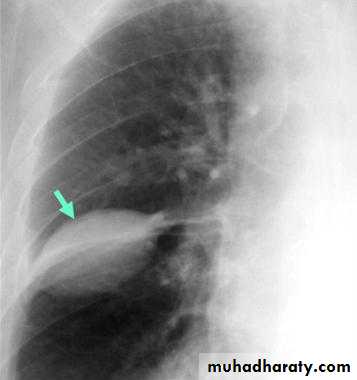

A subpulmonic effusion

(infrapulmonary effusion) accumulation of fluids between the lung & visceral pleura ..The following features are helpful :elevation of the hemidiaphragm ..right: peak of the hemidiaphragm is shifted laterally

left: increased distance between lower lobe air and gastric air bubble